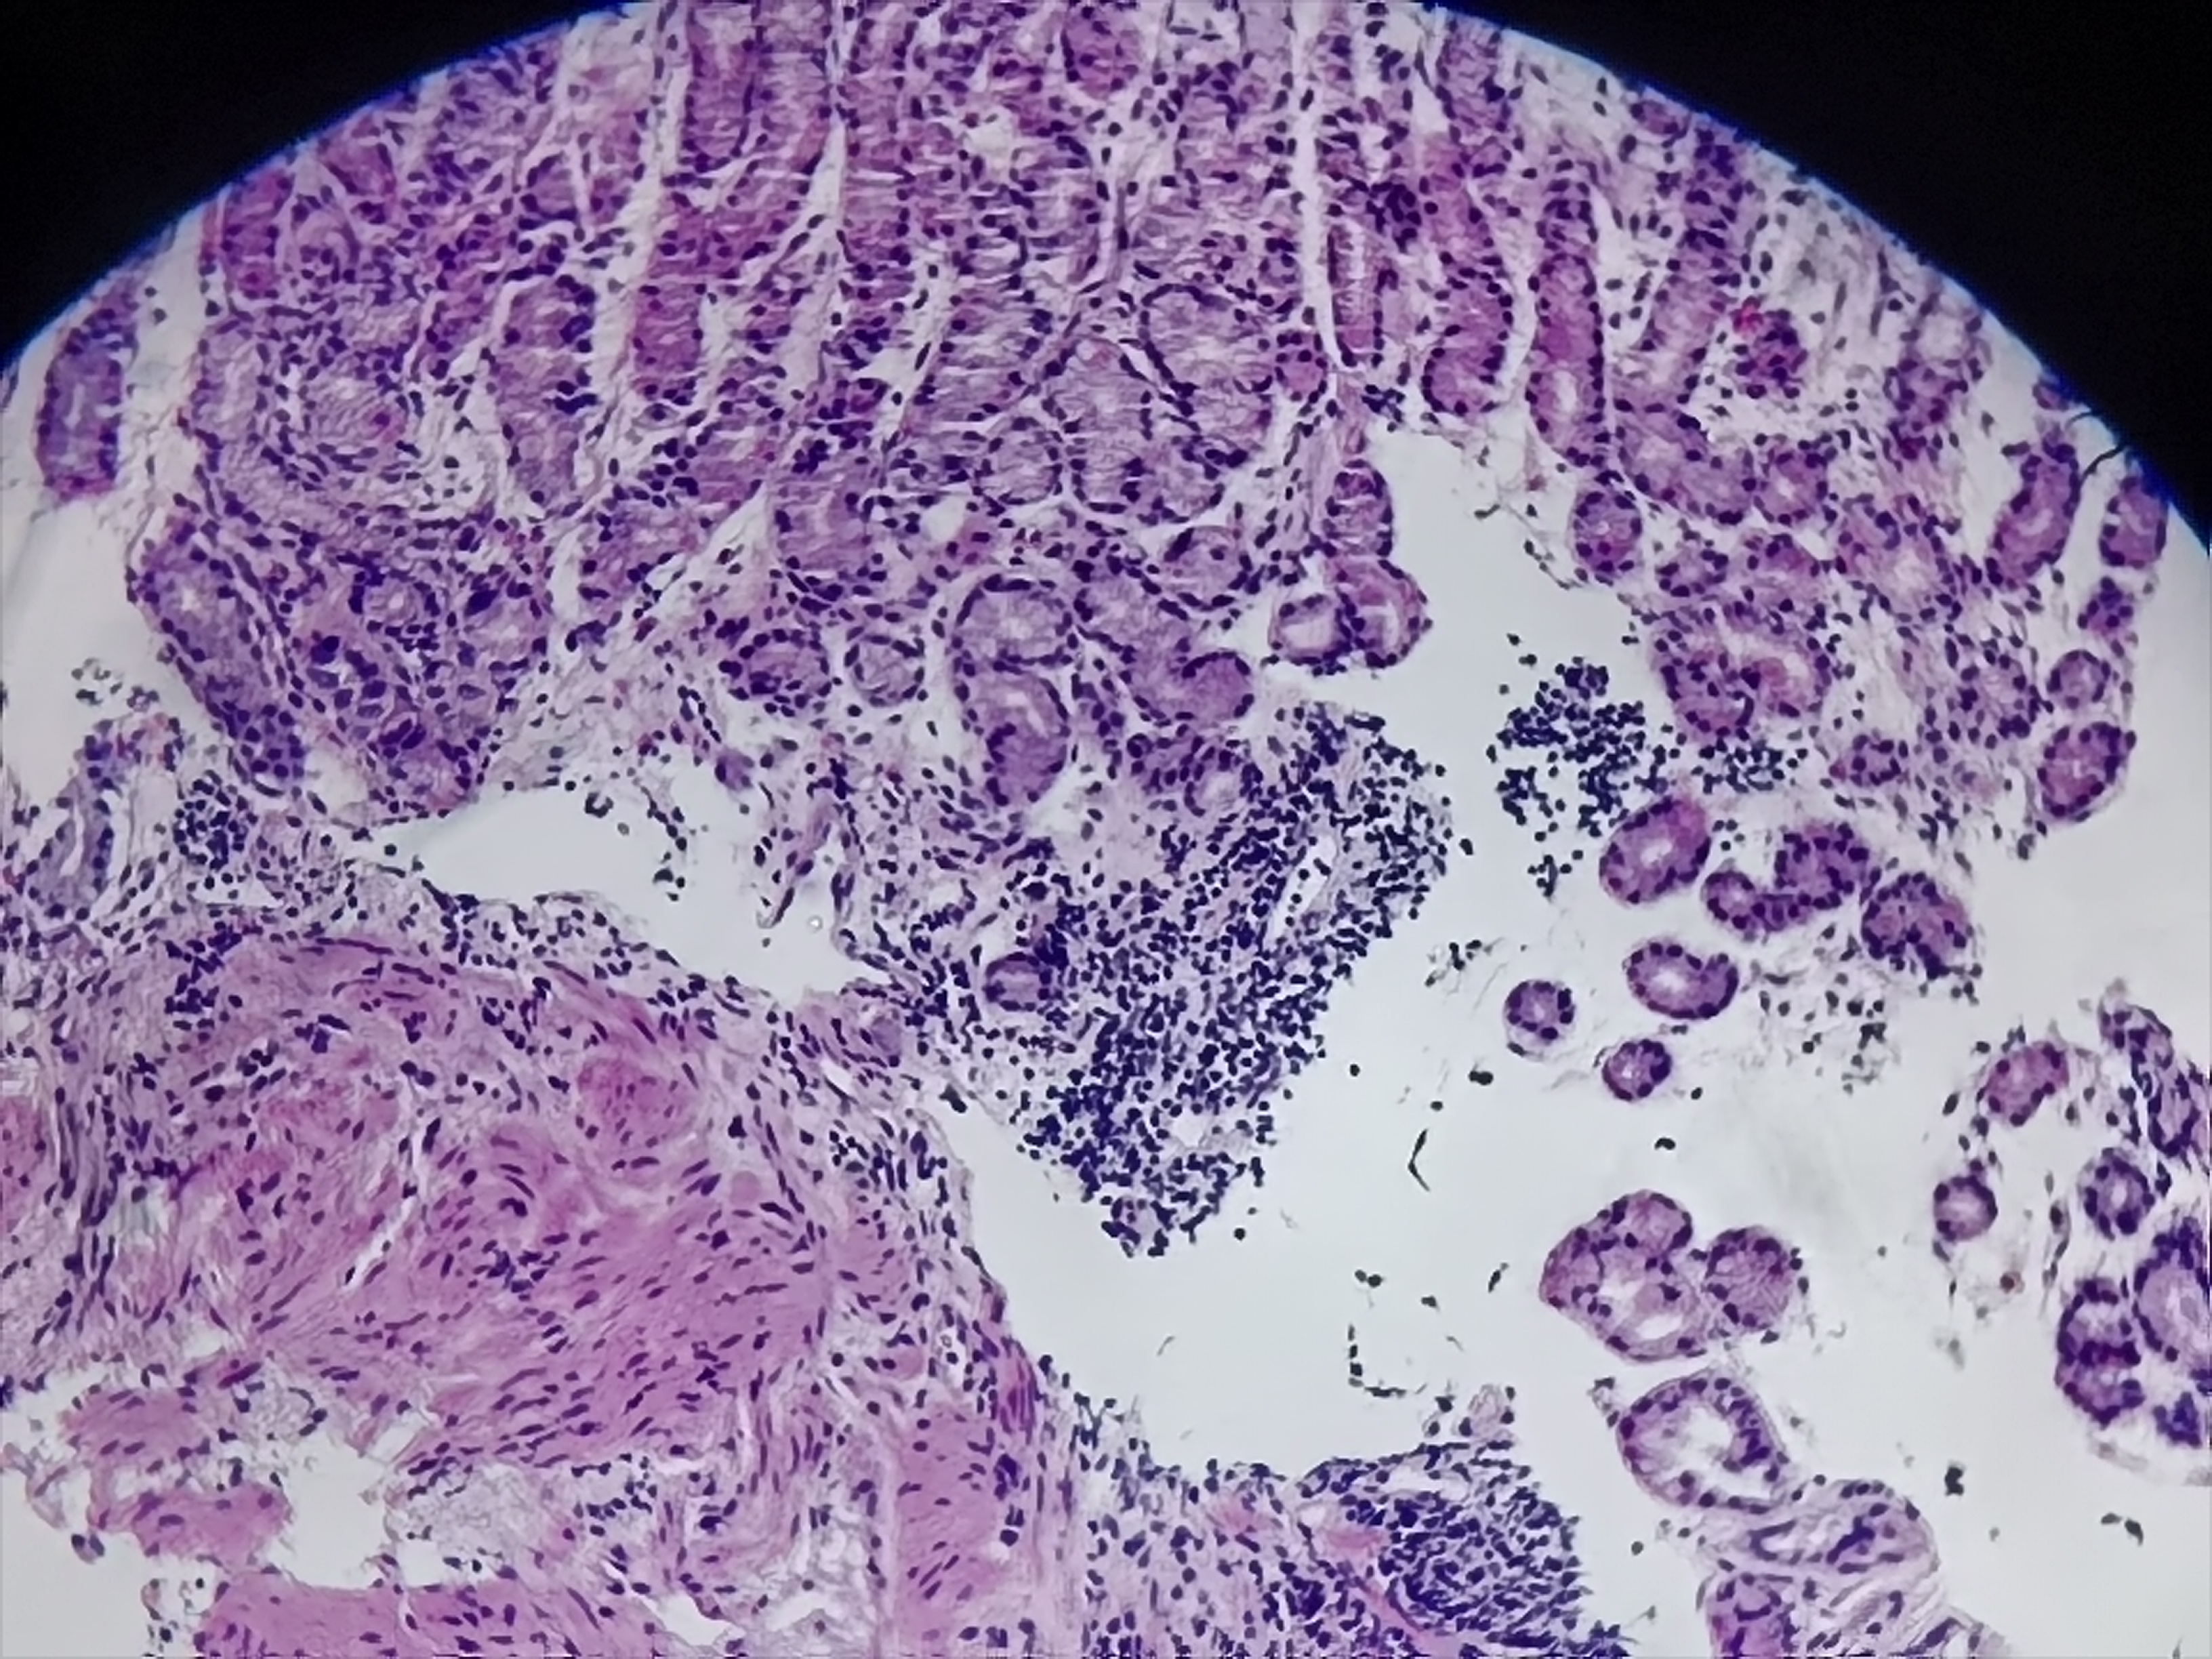

食管活检

食管:距门齿35cm至贲门口可见菜花样改变,有溃疡,触碰有出血

食管粘膜活检

灰白灰红组织3块

鳞皮乳头状增生伴粘膜慢性活动性炎,图11-14需要排除一下